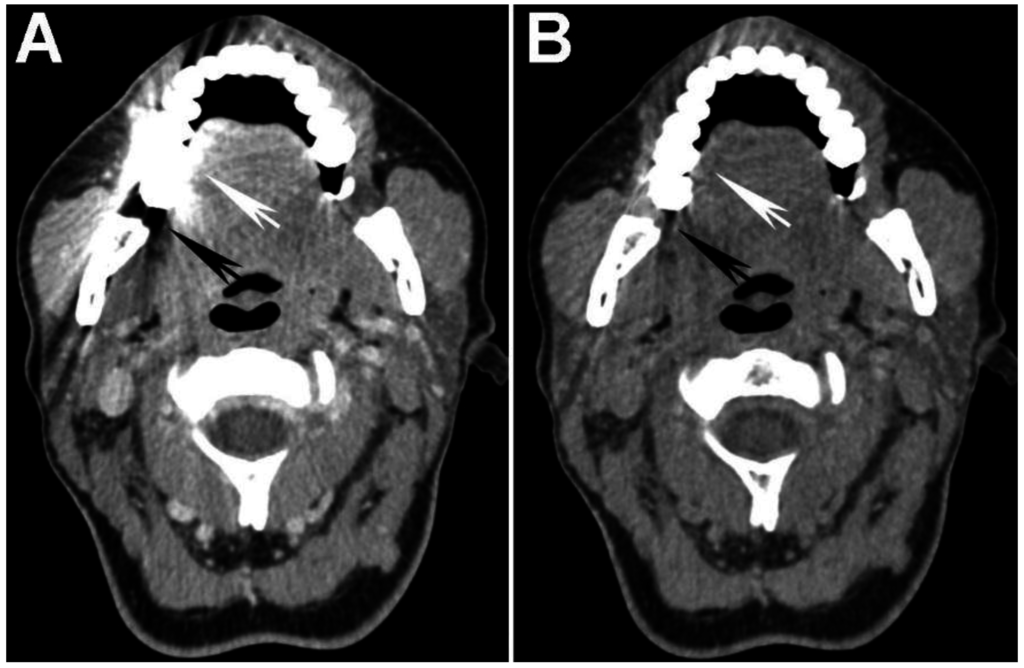

Figure 3. Virtual monochromatic images (VMIs) and iodine overlay map of a laryngeal tumor (T) invading the left thyroid cartilage. (A) 65 keV VMI; (B) 40 keV VMI; and (C) iodine-water (iodine overlay) material decomposition maps are shown. Note the increased tumor conspicuity on the 40 keV (B) compared to the 65 keV (A) VMIs. The iodine overlay map provides a quantitative estimate of iodine content of different tissues and demonstrates iodine containing tumor transgressing the left thyroid cartilage (arrow). It is noteworthy that the tumor edge of the extralaryngeal component (arrow) is more clearly seen on the 40 keV VMI (B) and iodine overlay map (C) than on the SECT equivalent 65 keV VMI (A).

DECT acquisitions enable creation of reconstructions based on two material or even three material decomposition [3,24]. These reconstructions can be used to isolate materials of interest relative to a reference material, assuming that the two materials have sufficiently different spectral properties. Two common types of reconstructions generated using material decomposition are maps reflecting the iodine content of different tissues, called iodine overlay maps, and virtual unenhanced images [3,24,38]. Iodine overlay maps are of interest in the assessment of HNSCC since they provide a quantitative estimate and a visual representation of the iodine content of different tissues, such as enhancing tumor (Figure 3).

In a study performed using a dual-source DECT, Kuno et al. [9] used iodine maps to help differentiate areas of tumor invasion from normal laryngeal cartilage (Figure 3). The authors showed that the addition of iodine overlay maps to the weighted-average (WA) equivalent of standard SECT 120-kVp images resulted in increased specificity (96% vs. 70%) for the diagnosis of invasion of laryngeal cartilage, without compromising the sensitivity (86% vs. 86%). These values show an improvement over those previously reported in the literature (83% specificity and 71% sensitivity) [48]. Furthermore, Kuno et al. also reported improved inter-observer reproducibility with the addition of iodine maps. Improved specificity and inter-observer reproducibility result in reduced overestimation of tumor invasion, and may help reduce unnecessary laryngectomies [9,46].